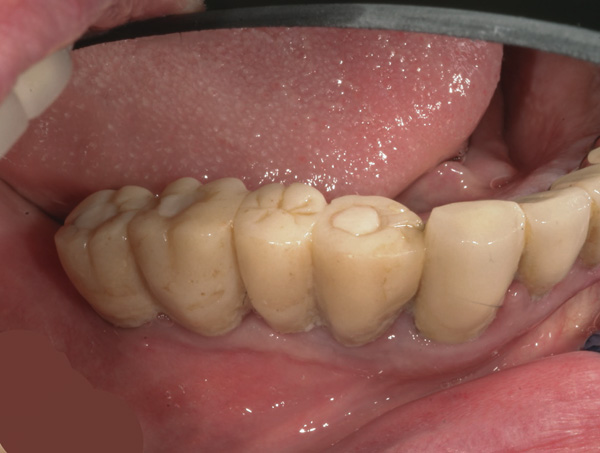

Results: The temporary cylinders screwed to the implants following placement are shown in Figure 13. They were luted to a prefabricated acrylic shell constructed from the patient’s diagnostic wax-up (Figure 14). Following removal of excess acrylic, the fixed screw-retained provisional prosthesis was inserted (Figure 15).

Figure 15 Fixed screw-retained provisional prosthesis.

Figure 15